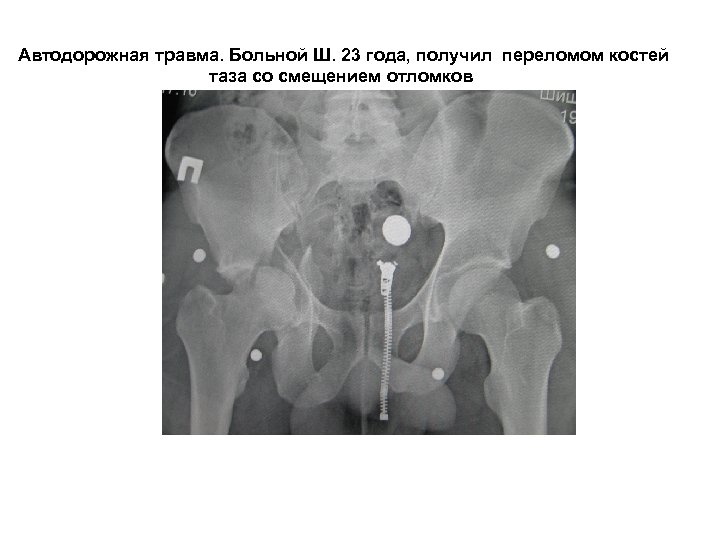

Автодорожная травма. Больной Ш. 23 года, получил переломом костей таза со смещением отломков

проведен остеосинтез перелома двумя тазовыми пластинами SYNTHES